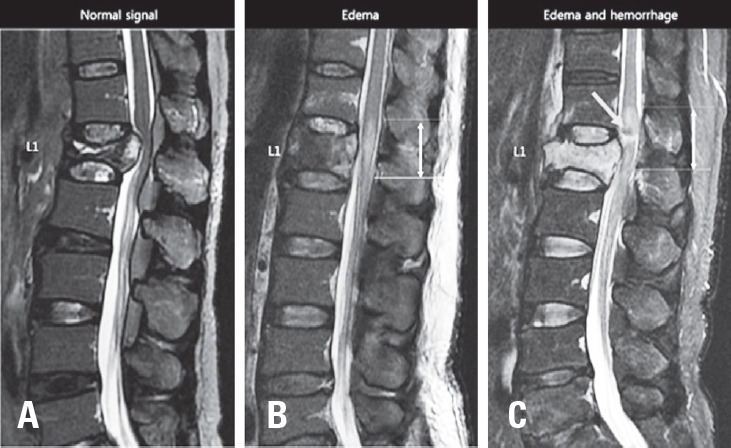

We performed retrospective cohort study evaluating 40 patients who presented to a level I trauma center between 2004 and 2017 with acute T-CMS and undergone a spinal surgical procedure. Diagnosis of T-CMS was made if all three criteria were met: (1) acute traumatic vertebral fracture in T12, L1, or L2; (2) the presence any neurologic deficit regarding CMS including leg weakness, decreased voluntary anal contraction, or sensory change in lower extremity or perianal area; (3) compression of CM or intramedullary signal change in CM on T2-weighted MRI (Fig. 1). The location of conus medullaris was confirmed on T1 and T2-weighted sagittal and axial images. Cases with compression of cauda equina (n=4) or compression or signal change in thoracic spinal cord (n=1) without involvement of CM were excluded.

T-CMS has unique clinical characteristics and prognosis differed from SCI and cauda equina syndrome. T-CMS patients have better neurologic recovery than SCI patients.17,18) and different type of bladder dysfunction.1) CMS has more symmetrical neurologic deficit and poorer neurologic recovery than cauda equine syndrome because CMS involves upper motor neuron.4,19) Clear diagnosis of T-CMS should be premised to identify the prognosis and related factors in T-CMS. Although some literatures diagnosed T-CMS with clinical findings,20-22) most literatures diagnosed T-CMS using the level of injury.4,7,18,23-26) Brouwers et al suggested the diagnosis of T-CMS with a trauma to vertebra T12–L2 in combination with neurological impairment in dermatomyotomes Th12–S54. Our study diagnosed T-CMS using this methods. Furthermore, we analyzed MRI images and excluded pure cauda equina injury and SCI (Fig. 1).

Fig. 1.

Diagnosis of acute traumatic conus medullaris syndrome on T2 weighted mid-sagittal MR image. (A) MR image of spinal cord injury showing acute vertebral fractures in T12, L1, and L2 with T2 hyperintensity on spinal cord without the involvement of conus medullaris. (B) MR image of conus medullaris syndrome showing acute vertebra fractures in T12 and L1 with T2 hyperintensity on conus medullaris. (C) MR image of cauda equine syndrome showing acute vertebral fracture in L2 with no involvement of conus medullaris. Bidirectional arrow represent whole length o conus medullaris.